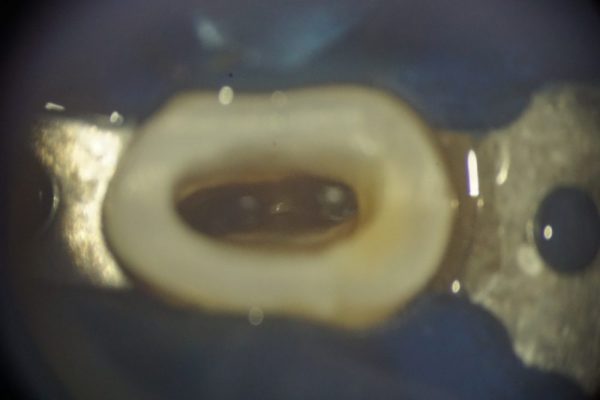

これは歯にラバーダム防湿を行い、歯を上から見た写真です。マイクロスコープで拡大した見ています。

これは歯にラバーダム防湿を行い、歯を上から見た写真です。マイクロスコープで拡大した見ています。

根の中に昔治療した材料が詰まっています。